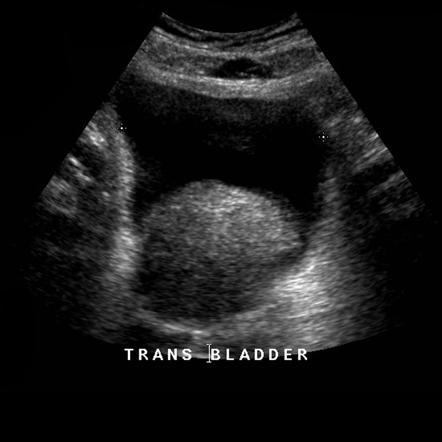

Scans:

•ultrasound

Confirmatory test:

Transrectal ultrasound